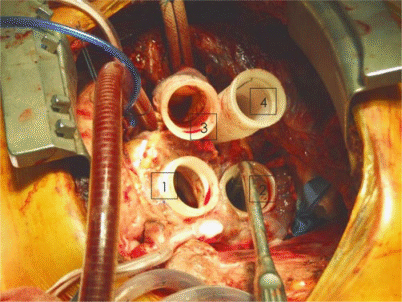

Der operative Ablauf – auf wenige, essenzielle Punkte reduziert – beginnt nach medianer Sternotomie und Etablierung der extrakorporalen Zirkulation durch eine Herz-Lungen-Maschine (HLM) mit der Resektion des irreversibel erkrankten Herzens auf der Ventrikelseite oberhalb der AV-Grube, wobei ein schmaler muskulärer Ventrikelsaum erhalten bleibt. Mitral- und Trikuspidalklappe werden bis auf einen 2-mm-Saum reseziert, Aorta und Truncus pulmonalis oberhalb der Klappen am sinotubulären Übergang quer durchtrennt. Der Koronarsinus wird an seiner Mündung in den rechten Vorhof vernäht. Filzarmiert werden nun „inflow connectors“ auf den muskulären Ventrikelsaum als atriale Cuffs aufgenäht. Mit diesen atrialen Manschetten müssen später die artifiziellen Pumpkammern konnektiert werden.

Bei allen Anastomosen muss auf eine absolute Hämostase geachtet werden

Die Ausflusstraktprothesen mit ihren Konnektoren werden in End-zu-End-Technik mit der aszendierenden Aorta und dem Truncus pulmonalis anastomosiert. Auf eine absolute Hämostase muss bei allen Anastomosen geachtet werden, da sie nach Einbringen der Pumpkammern nicht mehr einsehbar sind und potenzielle Blutungen nachträglich nur mit extremem Aufwand saniert werden können (Abb. 1).

Die mit physiologischer Kochsalzlösung gefüllten Ventrikel werden mit den atrialen Manschetten und den Ausflusstraktprothesen konnektiert (Abb. 2), zuerst die linke, schließlich die rechte Pumpkammer. Die Druckleitungen werden durch die Bauchdecke in der Regio epigastrica ausgleitet und mit dem pneumatischen Antrieb verbunden. Nach sorgfältiger Entlüftung werden die Pumpkammern niederfrequent angefahren, unter Überwachung mithilfe der transösophagealen Echokardiographie (TEE) wird über mehrere Minuten die Pumpfrequenz gesteigert, schließlich der Patient von der HLM entwöhnt. Volumen wird so verabreicht, dass ein zentralvenöser Druck von 12–15 mmHg erreicht wird und das TAH etwa 7 l/min pumpt. Die Füllung und Ejektion aus der Pumpe in den Kreislauf sind volumen- und vorlastabhängig und nehmen mit ansteigenden atrialen Drücken zu, d. h. je höher die Vorlast, desto höher das Herzzeitvolumen – ähnlich der Frank-Starling-Reaktion.

Abb. 2

Einbringen der linksventrikulären Pumpkammer in den Thorax. Gut ersichtlich sind die beiden Einscheibenprothesen in Mitral- und Aortenposition sowie die veloursbeschichtete Druckleitung, die später durch die Bauchdecke ausgeleitet wird